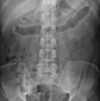

Large bowel obstruction

Small bowel obstruction